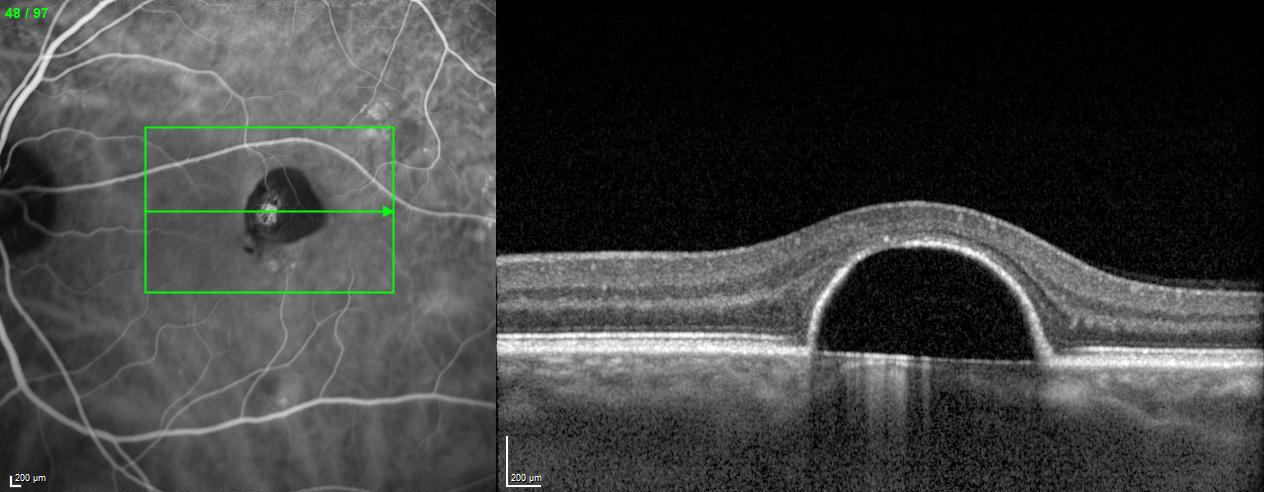

EDI – Enhanced Depth Imaging Mode

The Enhanced Depth Imaging Mode (EDI) of the SPECTRALIS is an OCT imaging technology that enables better visualization of choroidal vasculature. By automatically inverting the image and leveraging the benefits of technologies like TruTrack Active Eye Tracking and Noise Reduction, SPECTRALIS delivers superior images to depict the choroid, allowing to manually measure choroidal thickness.

Semi‐Automated Quantification of Retinal and Choroidal Biomarkers in Retinal Vascular Diseases: Agreement of Spectral‐Domain Optical Coherence Tomography with and without Enhanced Depth Imaging Mode